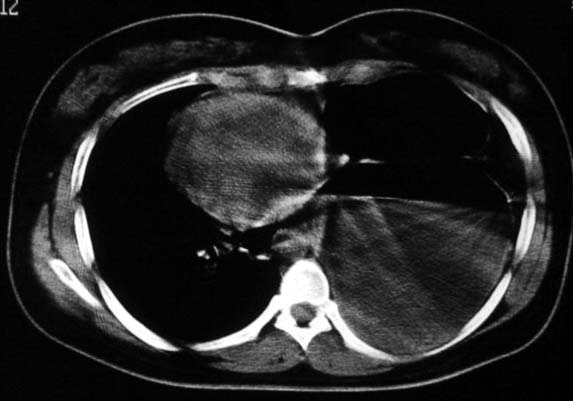

标题: CT5517:女性、24岁,反复胸痛、气促不能平卧半月。 [打印本页]

标题: CT5517:女性、24岁,反复胸痛、气促不能平卧半月。

左侧气液腔与胃腔影相连,考虑膈疝。钡餐检查有助于诊断。

我看这是膈疝,在纵隔窗第六\\七幅图像上可见胃粘膜影,再者可见两个腔影,这在液气胸是不会有的.

左侧气液腔与胃腔影相连,考虑膈疝。钡餐检查有助于诊断

支持膈疝,纵隔窗内可见消化道的内容物。

谨慎!喝钡透视一下吧。冒然报一液气胸,临床再穿刺引流结果把胃戳个大洞就麻烦了!